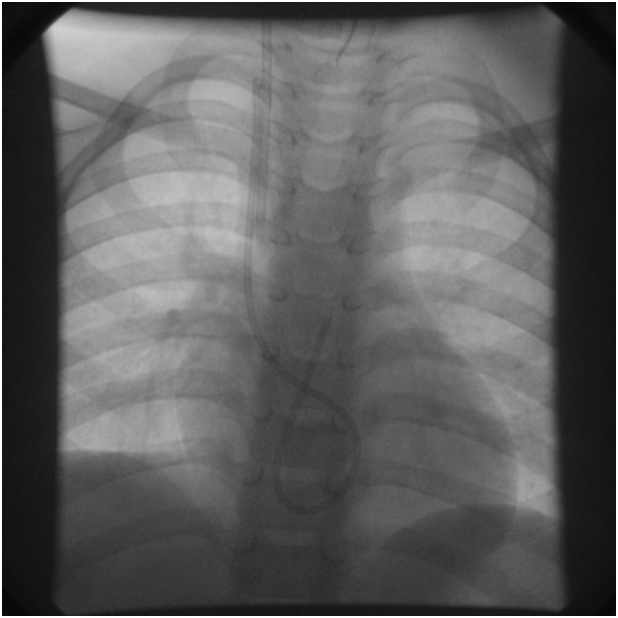

Nine months later and during routine follow-up, the patient presented with a history of trauma to the chest at the site of the Port-A-Cath which was found non-functioning and a chest radiograph showed that the catheter had been disconnected from the injection port and migrated into the heart (Figure 3). The patient was asymptomatic, admitted to the hospital and was kept under close monitoring. Disconnection of the catheter was suggested, so surgical intervention was performed and the injection port was removed successfully but due to difficult access it was recommended to remove the catheter by percutaneous retrieval technique after discussion with interventional cardiologist.

Figure 3 Shows the whole length of Port-A-Cath disconnected from its septum & migrated into the heart making a large curve in the right ventricle.